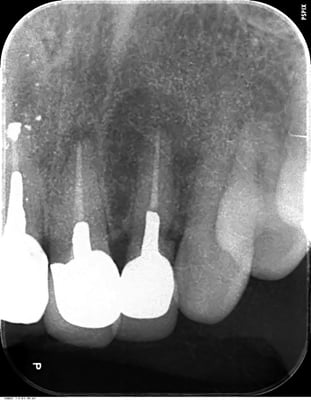

歯根端切除術 Apicopectomy

下顎前歯 root endo sealing

術後4年。